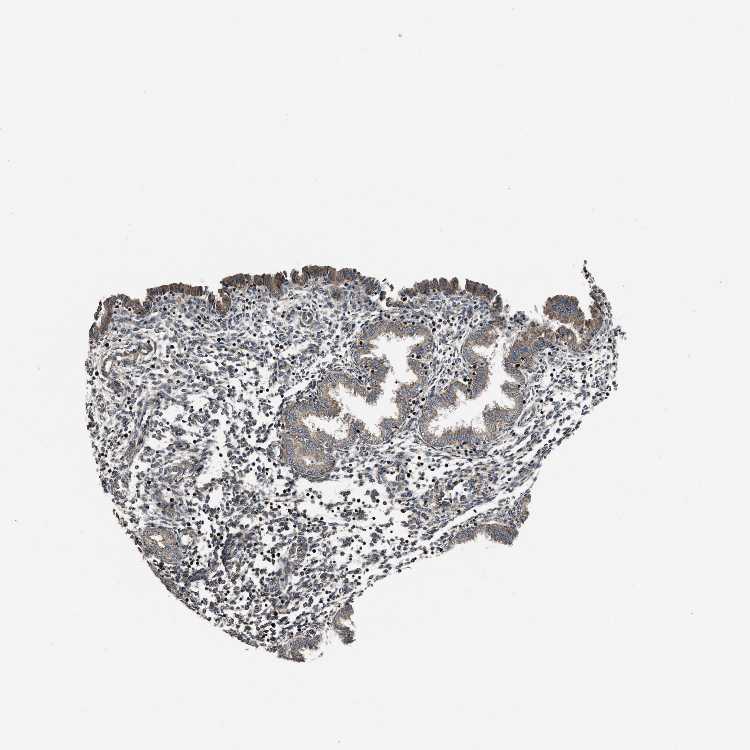

NSD3